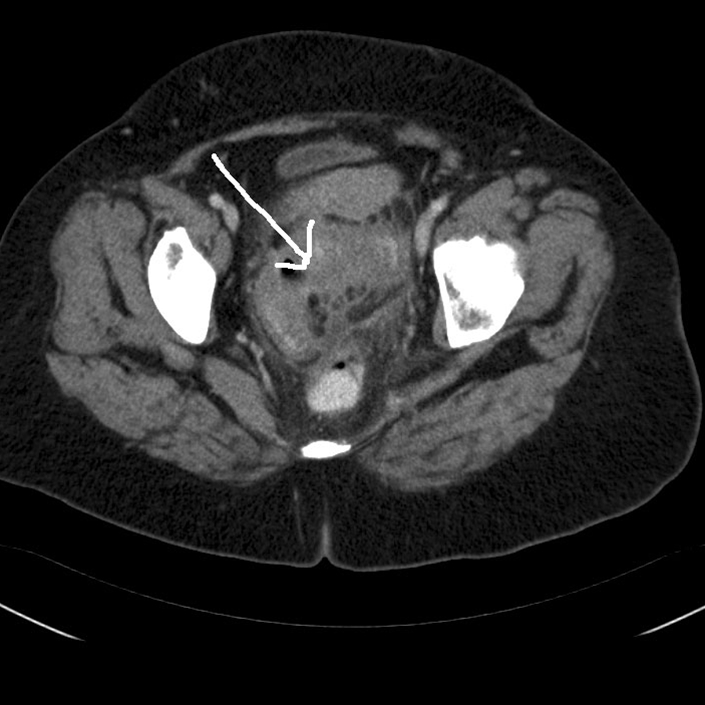

Diverticulitis i colon sigmoideum, tværsnit (CT)

CT scanning af abdomen, hvor et tværsnit viser diverticulitis i colon sigmoideum (pil angiver lokalisering).